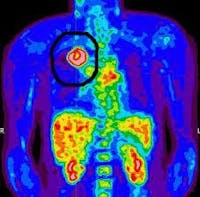

Otra idea errónea del efecto Warburg es que las células cancerosas solo pueden usar glucosa. Eso no es verdad. Hay dos moléculas principales que pueden ser catabolizadas por las células de los mamíferos: glucosa, pero también la proteína glutamina. El metabolismo de la glucosa se encuentra trastornado en el cáncer, pero también lo está el metabolismo de la glutamina. La glutamina es el aminoácido más común en la sangre y muchos cánceres parecen ser “adictos” a la glutamina para sobrevivir y proliferar. El efecto se ve más fácilmente en la exploración de tomografía de emisión de positrones (TEP). Las tomografías por emisión de positrones (TEP) son una forma de imagen que se usa mucho en oncología. Se inyecta un marcador radiactivo en el cuerpo. La exploración TEP clásica utiliza flúor-18 fluorodesoxiglucosa (FDG), que es una variante de la glucosa normal, marcada con un marcador radioactivo para que pueda ser detectada por el escáner TEP.

La mayoría de las células absorben glucosa a una tasa basal relativamente baja. Sin embargo, las células cancerosas absorben la glucosa igual que un camello consume agua después de una caminata por el desierto. Estas células de glucosa marcadas se acumulan en el tejido canceroso y pueden verse como lugares activos de crecimiento del cáncer.